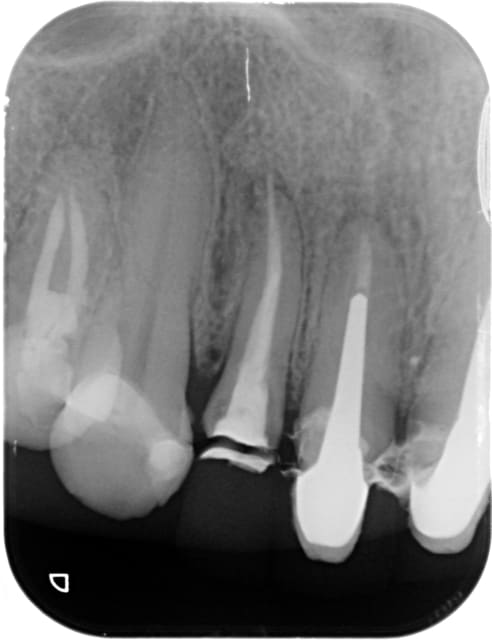

une autre 22.

lésion apicale avec fistulisation il y a quelques semaines.

1/ Dépose de la couronne à tenon dans le cadre d'une réhabilitation prothétique globale des prothèses car racines marrons apparentes dans le sourire. odeur --- rockles sur coton. pansement.

radio post OP. et la le doute , la raison de mon post...

image hélicoïdale à l'apex.

je vérifie le lentulo, je le compare avec ses semblables.

Il ne manque rien.

La pâte à laissé la trace du lentulo on jurerait qu'il y en a un bout, vous confirmez? vous avez déjà remarqué ça ?

Je ne vois pas de lentulo, par contre ça ressemble à un dépassement de cône de gutta.

Hors sujet peut être, mais faudrait aussi traiter la 21, et vu le délabrement radiculaire cervical prévoir une bonne élongation coronaire pour 22 et 21, et sensibiliser le patient à l'implanto, car à mon avis c'est pour bientôt.